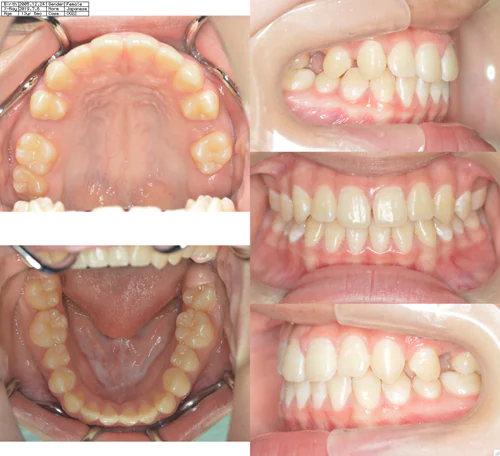

case.4(山本 雪月花様)

治療前 治療中 治療後

治療開始の年齢 12歳6ヶ月

治療名 上顎両側5番開窓牽引

異所萌出している5番を開窓牽引した

治療内容 全顎的な矯正

費用 770,000円

治療期間 1年6ヶ月